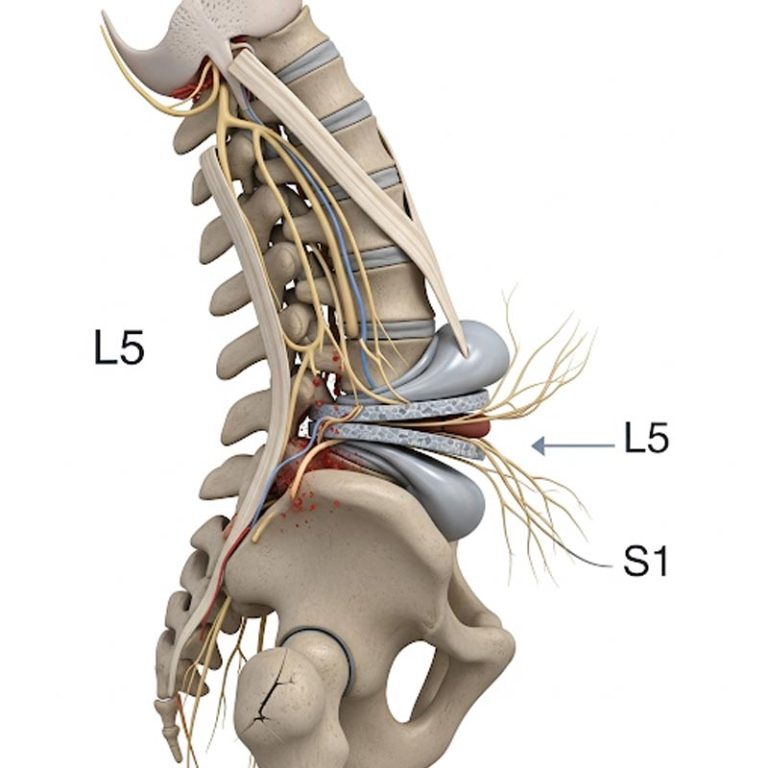

Spondylolisthesis is a spinal condition where one vertebra slips forward over the one below it, often...

A slipped disc, also called a herniated disc, occurs when the soft inner gel of a spinal disc pushes...